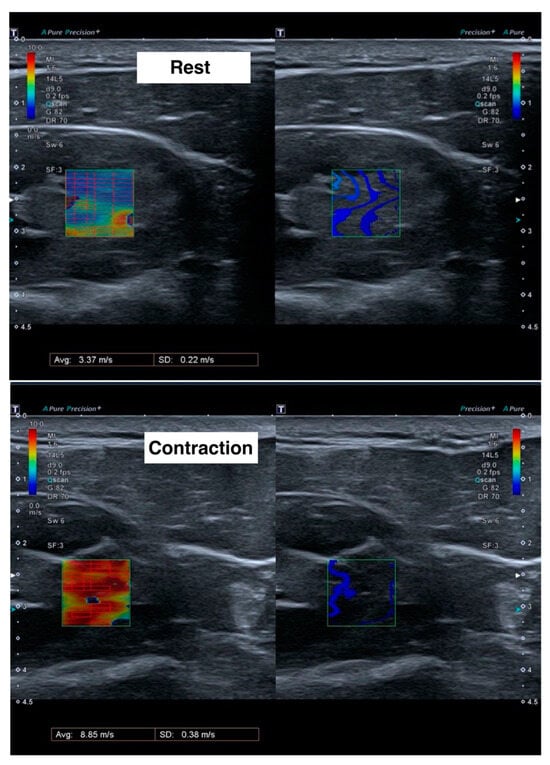

For each measurement, the mean velocity (m/s) and standard deviation of the region of interest was calculated (Figure 1). The final value for each subject was calculated as the weighted mean of the three measurements, using the inverse of the standard deviation as the weights.

Figure 1. Ultrasound images during shear wave elastography measurements at rest (upper) and during contraction (lower). Left images show the velocity of the shear waves in meters per second, with red color meaning more speed and blue color less speed. Right images show the form of the shear wave.